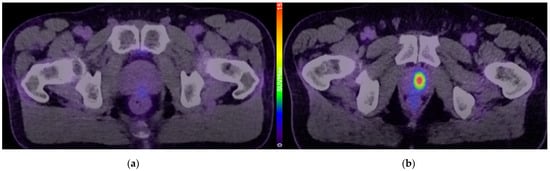

- Pepe, P.; Pepe, L.; Tamburo, M.; Marletta, G.; Savoca, F.; Pennisi, M.; Fraggetta, F. 68Ga-PSMA PET/CT evaluation in men enrolled in prostate cancer Active Surveillance. Arch. Ital. Urol. Androl. 2023, 95, 11322. [Google Scholar] [CrossRef]

- Heetman, J.G.; Lavalaye, J.; Polm, P.D.; Soeterik, T.F.W.; Wever, L.; Paulino Pereira, L.J.; van der Hoeven, E.; van Melick, H.H.E.; van den Bergh, R.C.N. Gallium-68 Prostate-specific Membrane Antigen Positron Emission Tomography/Computed Tomography in Active Surveillance for Prostate Cancer Trial (PASPoRT). Eur. Urol. Oncol. 2024, 7, 204–210. [Google Scholar] [CrossRef]

- Jain, A.; Nassour, A.J.; Dean, T.; Patterson, I.; Tarlinton, L.; Kim, L.; Woo, H. Expanding the role of PSMA PET in active surveillance. BMC Urol. 2023, 23, 77. [Google Scholar] [CrossRef]